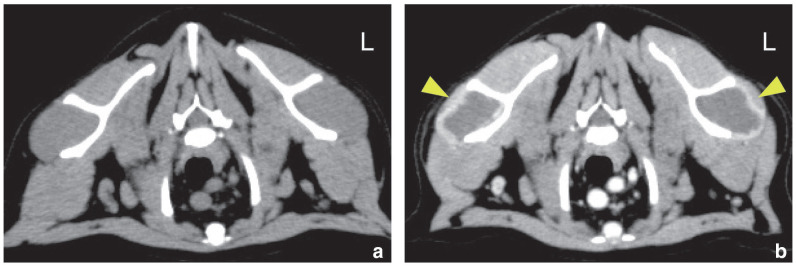

Case summary: Persistent and progressive weakness secondary to hypokalaemia, that is, hypokalaemic polymyopathy, is one of the most common clinical signs of primary hyperaldosteronism (PHA). Herein, we report a case of PHA with infraspinatus muscle necrosis. A 5-year-old castrated male domestic shorthair cat presented with a history of polyuria and polydipsia, decreased activity, staggering gait, difficulty in jumping and inward rotation of both forelimbs. Blood examination revealed hypokalaemia, increased serum creatinine kinase activity and high serum aldosterone concentration. Abdominal ultrasonography and CT revealed an enlarged right adrenal gland. Post-contrast thoracic CT showed peripheral contrast enhancement and a non-enhanced centre in the bilateral infraspinatus muscles. From the day of initial presentation, the cat was started on oral potassium replacement therapy. On day 17, the right adrenal gland was surgically resected and the left infraspinatus muscle was biopsied. Histopathological examination confirmed the presence of an adrenocortical adenoma in the right adrenal gland and necrosis of the muscle fibres in the left infraspinatus muscle. On day 29, all clinical signs had disappeared, and the serum potassium concentration, creatinine kinase activity and aldosterone concentration had normalised. On day 57, atrophy of the bilateral infraspinatus muscles was noted, but there was no evidence of any posture or gait abnormalities.